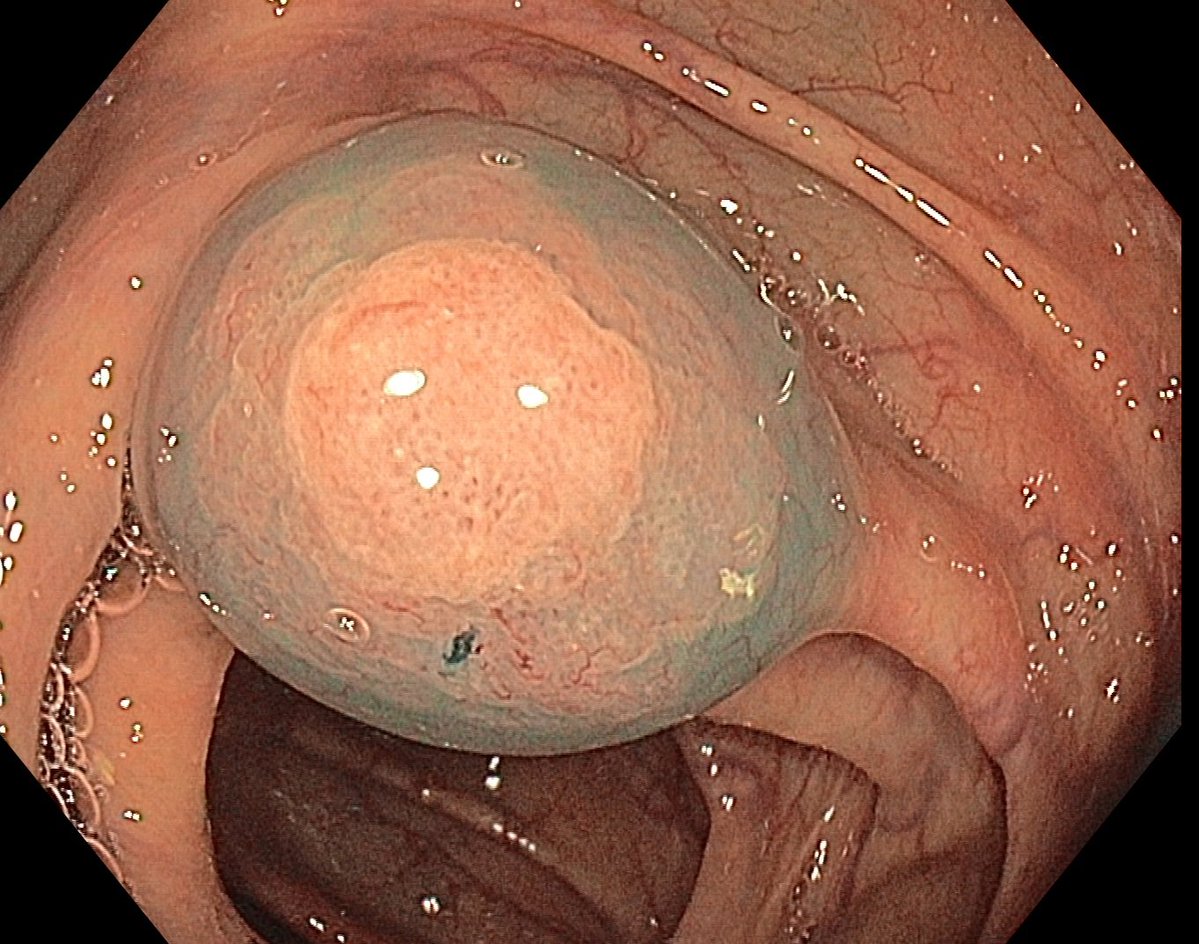

📢 March 2026 Issue #ACGCRJ 📷: Endoloop assisted hot snare polypectomy of a large brunner gland hamartoma in distal duodenum using colonoscope.🔦 🔗journals.lww.com/acgcr/pages/cu… @DushDahiya @DaniyalAbbasMD @AmCollegeGastro